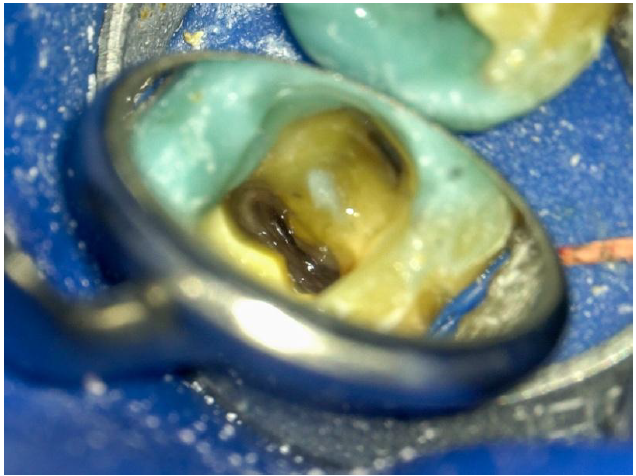

Following removal of the existing crown on tooth 47, retreatment was initiated using the Neoniti C1 file (450 RPM, 2.5 N·cm) and ultrasonic instruments to begin gutta-percha removal. The consistency of the gutta-percha resembled plastic, necessitating the use of Neolix files, which performed exceptionally in this scenario.

Aspect of the pulp chamber after removing the crown and coronal filling

All existing composite restorations were removed to assess underlying structural integrity. Extensive decay was found beneath the lingual composite wall, which was subsequently restored using a contrast shade core build-up (Encore DC MiniMix) with a dual-cure adhesive (Connexio). Due to time constraints, calcium hydroxide was placed as an intracanal medicament before final obturation.

Decay present under the old composite filling